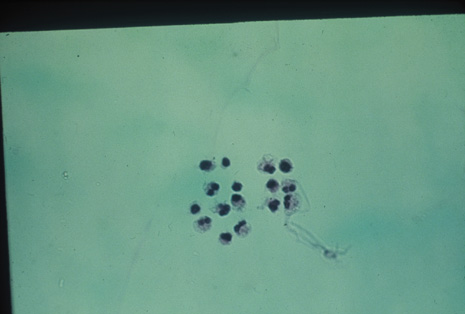

Although keratocentesis had been advocated historically as a treatment for active uveitis, it lost the attention of ophthalmologists until 1919, when Bruckner3 first examined the aqueous humor for diagnostic purposes. Laboratory techniques were revolutionized in the 20th century in areas such as: (a) evaluating very small aliquots of fluid (0.2 to 0.3 mL of aqueous or vitreous), and (b) identifying specific microbial organisms and the predominance of other cell types, antibodies, and proteins in these fluids (Figs. 1, 2, 3, 4, 5, and 6). These advancements have led to the development of diagnostic paracentesis for sight-threatening ocular inflammations that are difficult to diagnose. Witmer4 and O'Connor5 have provided strong evidence that samples of the aqueous humor reflect the antibody-producing capabilities of the iris and ciliary body, particularly when more specific antibody per unit of gamma globulin can be found on the aqueous humor than in the blood of the same patient.6–8 These determinations may be highly significant when one considers the fact that diseased tissue is being bathed in an antibody-containing fluid that is elaborated locally. For instance, in the case shown in Figure 1, the immunofluorescent antibody titer to toxoplasmosis is four times greater in the vitreous aspirate at the time of vitrectomy for repair of retinal detachment than in the plasma. These same considerations have long been recognized in syphilis of the central nervous system, wherein specific antibodies may be present in the cerebrospinal fluid but not in the blood. This is also the case with an unusual presentation of ocular coccidioidomycosis9 or toxocariasis.

Many forms of uveitis are characterized by specific types of inflammatory cells. Usually, however, one encounters mixtures of cell types in any given specimen, with the relative percentages of lymphocytes and polymorphonuclear leukocytes varying. There may be unusual numbers of eosinophils, or macrophages laden with lens material may be present. Thus, an enumeration of the cells and a careful analysis of their structure can be useful as a diagnostic aid (Figs. 7, 8, 9, 10, 11, 12, 13, 14, 15, 16, 17, 18, 19, and 20). Figure 15 demonstrates eosinophils that were aspirated from the anterior chamber of a patient with Toxocara canis endophthalmitis. Figure 12 demonstrates malignant cell infiltrate from the vitreous, showing the stained presence of monoclonal light chains being elaborated in the cytoplasm. Interleukin-10, detectable in the vitreous of intraocular lymphoma patients, is also directly indicative of both the clinical activity and the number of malignant cells as observed by cytopathology.

Precise identification and culture of bacterial and fungal pathogens from both the aqueous humor and the vitreous fluid can be obtained. Gram's stain and Giemsa's stain smears of centrifuged specimens from the aqueous humor and the vitreous humor frequently demonstrate the bacterial or fungal causative agent. Attempts to isolate bacteria and fungi and to identify them on Gram's stain or Giemsa's stain smears have been most rewarding in the following cases: (a) postoperative endophthalmitis, (b) infection after a penetrating injury of the eye, (c) drug abuse patients with endogenous endophthalmitis (Figs. 21, 22, 23, 24, and 25), (d) patients receiving hyperalimentation, and (4) patients who are immunocompromised as a result of exogenous immunosuppressive agents.